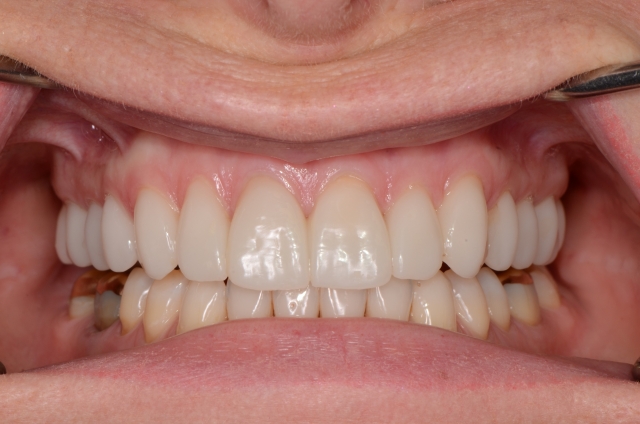

We designed the teeth to be restored and fabricated milled provisionals by scanning the wax-up and creating a set of PPMA (Anaxdent Multi) provisional restorations. These served as the “appliance” to test our theory regarding the stability of the restorations. We bonded the milled provisionals and gave the patient the opportunity to test the new occlusion for about three months.

The provisionals remained completely stable. The patient noted these changes and told me that she felt much more relaxed, more rested, more comfortable, more confident. Stability is a beautiful thing.